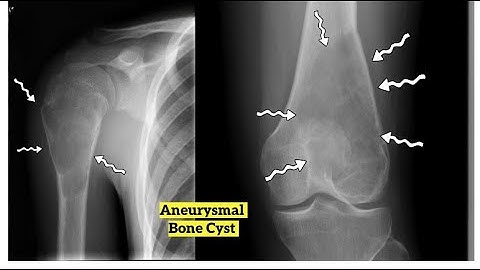

The Use of Demineralized Bone Matrix and MSC Concentration for the Treatment of the Bone Cysts